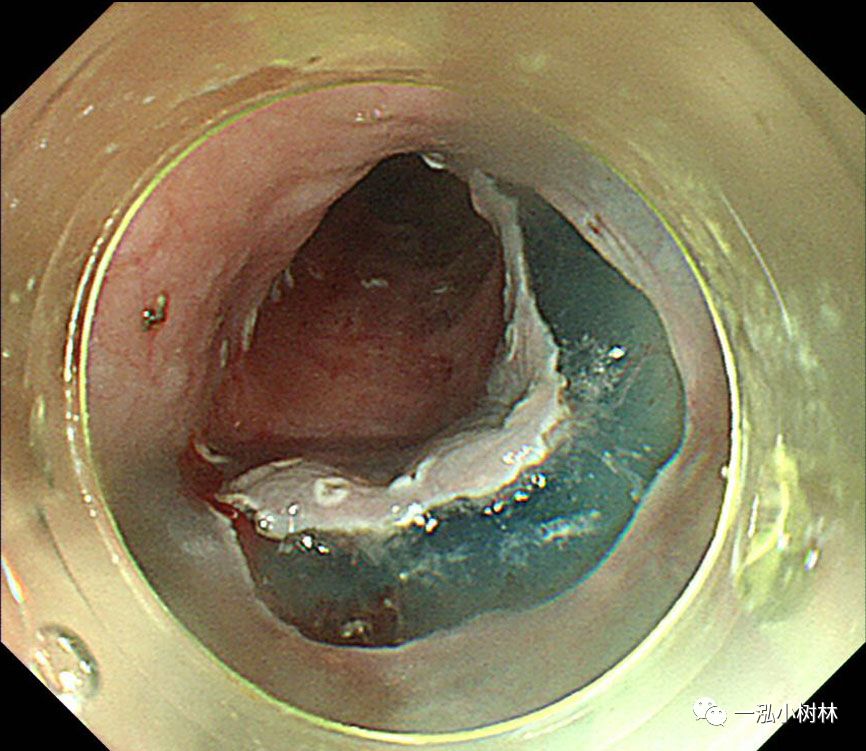

图4 用Dual刀在病变外5mm处标记